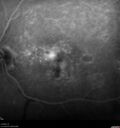

Pattern dystrophy with progressive foveal atrophy left eye

72 year old man. Vision in the left eye is 20/80. It declined to 5/200 over about 3 years.